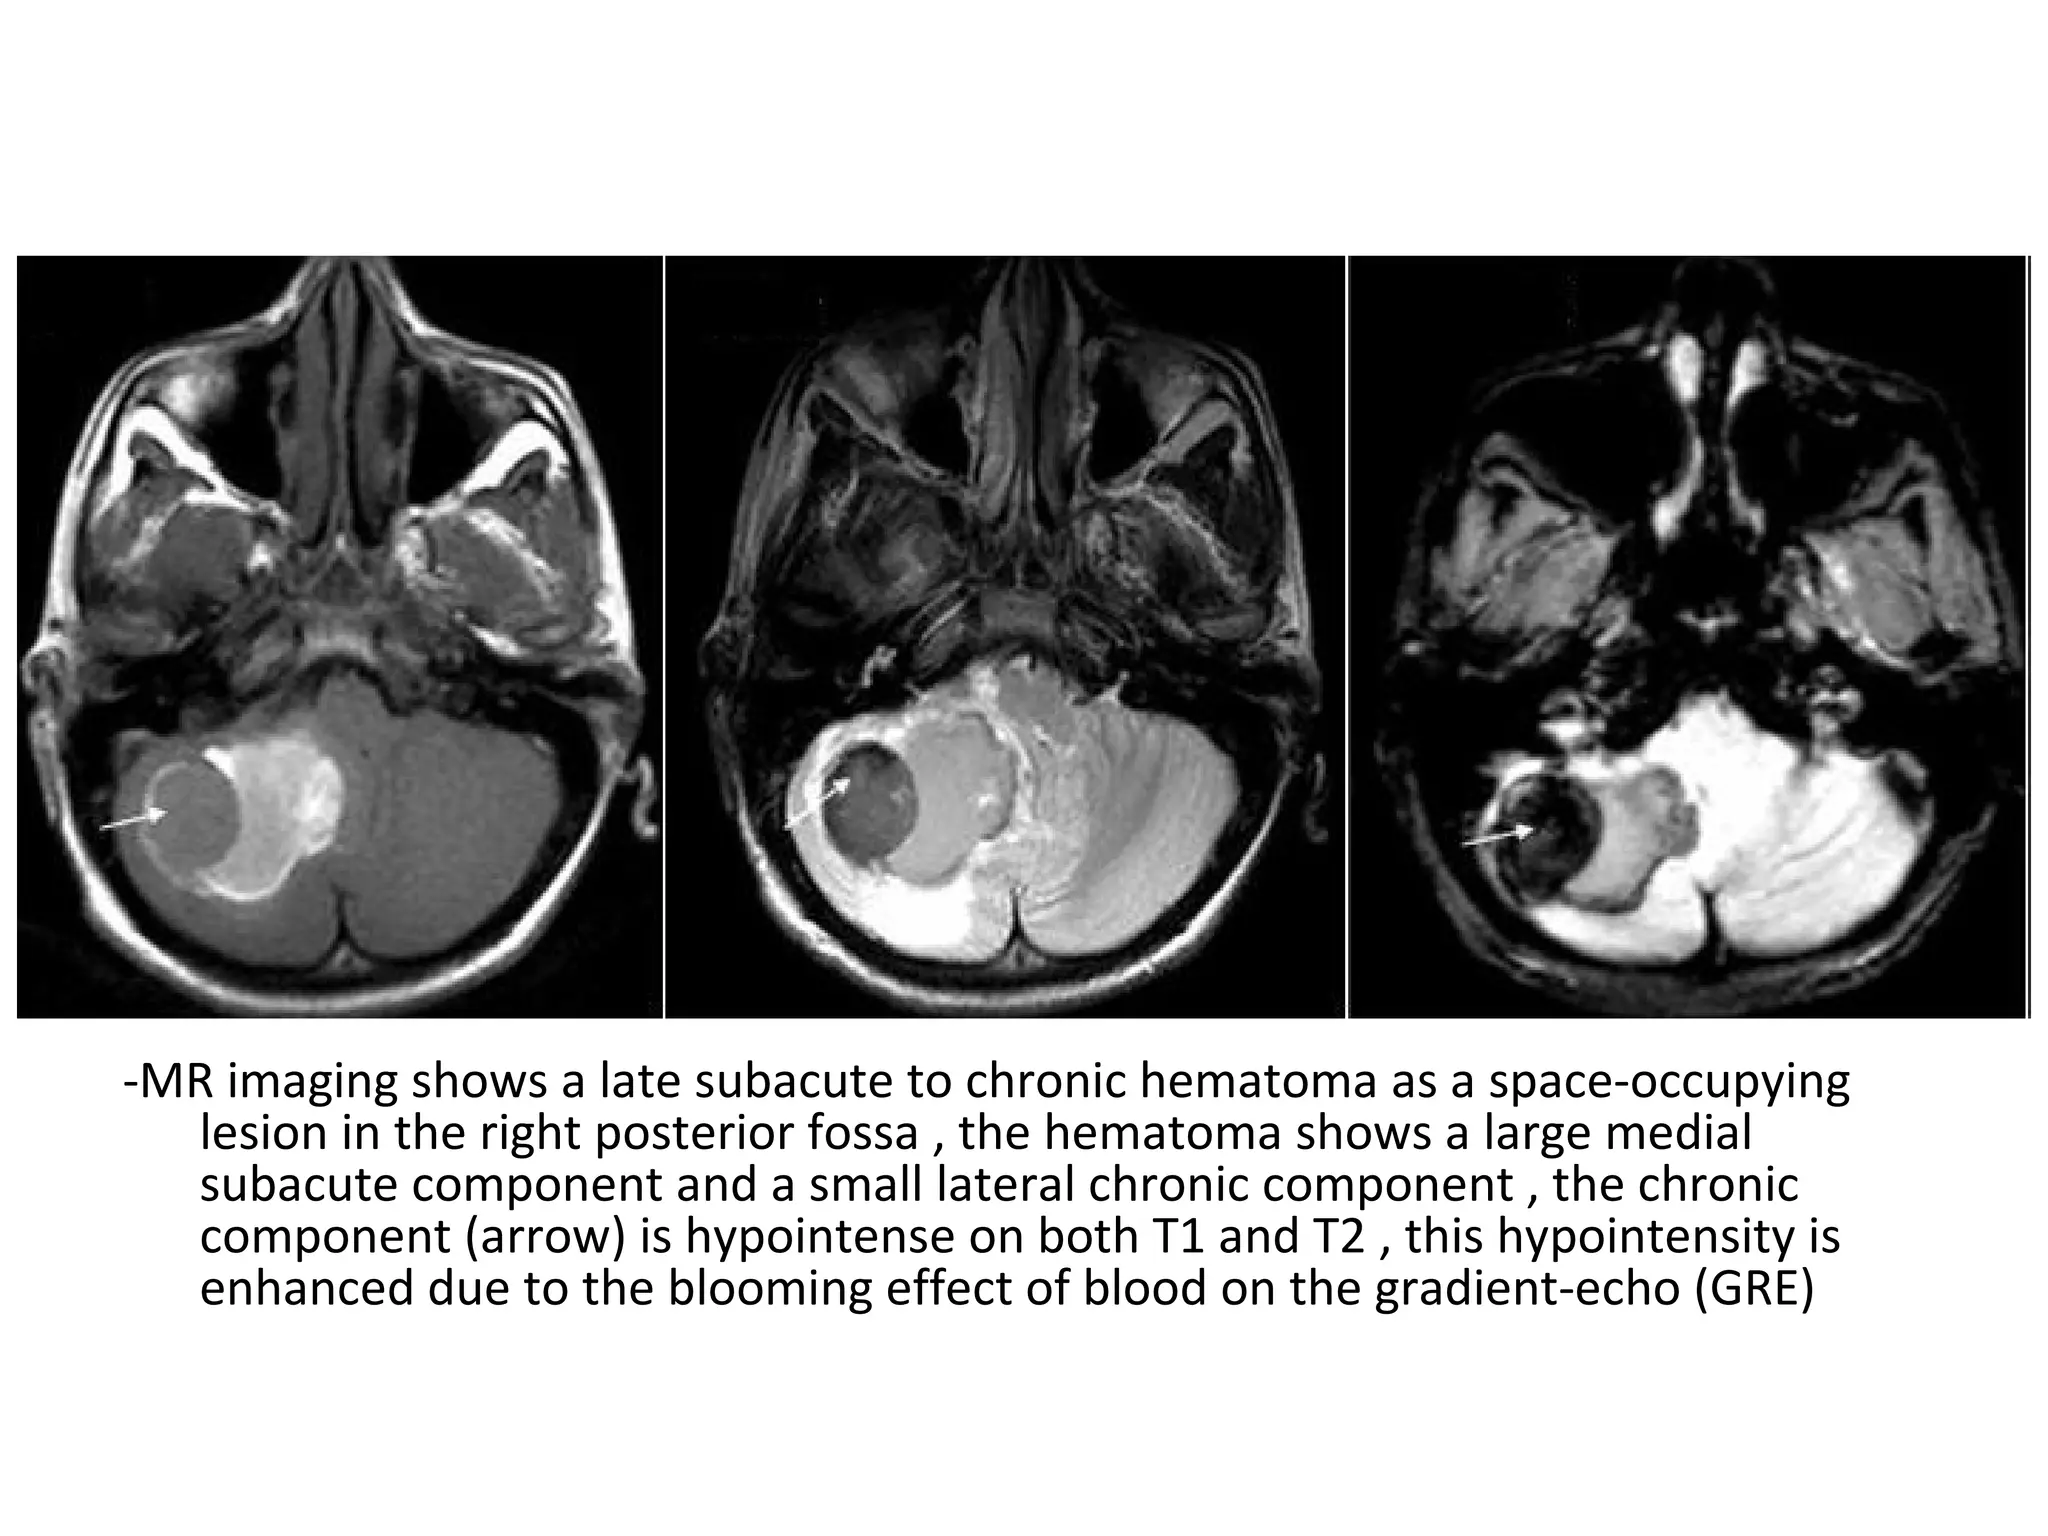

5-Mass Effect :

-Current diagnosis of CVI relies on the detection

of parenchymal edema or hemorrhage in the

presence of acute cerebral venous thrombosis

-Marked brain swelling is often seen with

venous infarction , even on day 1

-Arterial infarcts usually show maximal swelling

at 3-5 days

A: T1 showing slightly swollen right frontal cortex and no signal change

B : T2 depicting a ring of signal hyperintensity in right frontal cortex

C : Diffusion revealing a more hyperintense right frontal cortex than B

D : ADC showing corresponding decrease suggesting cytotoxic edema

-Cytotoxic cerebral edema refers to a type

of cerebral edema in which the blood brain

barrier (BBB) is intact (c.f. vasogenic cerebral

edema where BBB is lost) , it is an intracellular

edema which mainly affects grey matter but

also involves the white matter , it is due to a

cellular swelling from lack of ATP , that is

typically seen in area of cerebral ischemia or

cerebral hypoxia

MRI : Hyperintense T2 and FLAIR signals which

characteristically shows restricted diffusion

CT : Loss of grey white matter differentiation (as

it mainly affects grey matter) , effacement of

sulcal spaces

DW

-Vasogenic cerebral edema refers to a type

barrier (BBB) is disrupted , it is an extracellular

edema which mainly affects the white matter ,

through leakage of fluid out of capillaries , it is

most frequently seen around brain tumors (both

primary and secondary) and cerebral abscesses ,

although some vasogenic edema may be seen

around maturing cerebral contusion and cerebral

hemorrhage

CT : Grey-white matter differentiation is

maintained and the edema involves mainly white

matter , extending in finger-like fashion ,

secondary effects of vasogenic edema are similar

to cytotoxic edema with effacement of cerebral

sulci with or without midline shift

MRI : Hyperintense T2 and FLAIR signals which do

not show restricted diffusion

(c.f. cytotoxic cerebral edema which shows

diffusion restriction)

6-Dural Thickening :

-The empty delta sign of peripheral

enhancement around a central core of acute

thrombus represents hypervascularity and

engorgement of the dura , not a patent

peripheral channel

-Persistent dural thickening is a feature of

subacute / chronic venous thrombosis

7-Imaging In Suspected Thrombosis :

a) CT venography

b) MR venography

c) DSA

a) CT Venography :

-CT venography is a simple and straight forward

technique to demonstrate venous thrombosis

-In the early stage there is non-enhancement of

the thrombosed vein and in a later stage there

is non-enhancement of the thrombus with

surrounding enhancement known as empty

delta sign

-Unlike MR , CT venography virtually has no

pitfalls , the only thing that you don't want to

do , is to scan too early , i.e. before the veins

enhance or too late , i.e. when the contrast is

gone , some advocate to do a scan like a CTA

and just add 5-10 seconds delay , to be on the

safe side better to advocate 45-50 seconds

delay after the start of contrast injection , use

at least 70 cc of contrast

Infarction in the area of the vein of Labbe, on the non-enhanced images you can appreciate the

dense thrombus within the transverse sinus and the hemorrhage in the infarcted area, on the

enhanced images a filling defect can be seen in the transverse sinus

b) MR Venography :

-The MRI techniques that are used for the

diagnosis of cerebral venous thrombosis are :

1-Time of Flight (TOF)

2-Phase Contrast Angiography (PCA)

3-Contrast Enhanced MRV

1-Time of Flight (TOF) :

-MRI technique to visualize flow within vessels ,

without the need to administer contrast

-It is based on the phenomenon of flow-related

enhancement of spins entering into an

imaging slice

-As a result of being unsaturated , these spins

give more signal that surrounding stationary

spins

-With 2-D TOF , multiple thin imaging slices are

acquired with a flow-compensated gradient-

echo sequence , these images can be

combined by using a technique of

reconstruction such as maximum intensity

projection (MIP) to obtain a 3D image of the

vessels analogous to conventional

angiography

-With 3D TOF , a volume of images is obtained

simultaneously by phase-encoding in the slice-

select direction , an angiographic appearance can

be generated using MIP as is done with 2-D TOF

-Several 3D TOF volumes can be combined to

visualize longer segments of vessels , 3D TOF

angiography will allow greater spatial resolution

in the slice-select direction than 2D TOF ,

however , with thick volumes and slow flowing

blood, loss of signal is seen with the 3-D TOF

method

1 =superior sagittal

sinus

2 = straight sinus

3 = torcular herophili

5 = lateral (transverse)

6 = sigmoid sinus

7 = internal jugular

vein

-The arrows point to

superficial cerebral

veins

1 =superior sagittal sinus

4 = vein of Galen

5 = lateral ( transverse )

7 = internal jugular vein

8 = internal cerebral vein

9 = basal vein of Rosenthal

The arrows point to

superficial cerebral veins

2-Phase contrast angiography (PCA) :

-Uses the principle that spins in blood that is

moving in the same direction as a magnetic field

gradient develop a phase shift that is

proportional to the velocity of the spins

-This information can be used to determine the

velocity of the spins , this image can be

subtracted from the image that is acquired

without the velocity encoding gradients to obtain